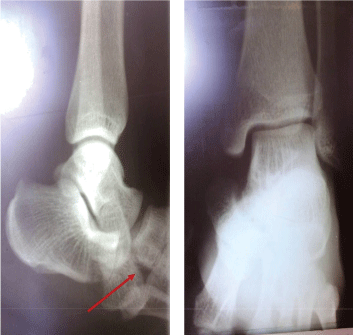

A right foot/ankle X-ray requested and a CT scan showed a medial dislocation of the talonavicular joint without fracture (Figure 1a and Figure 1b).

Figure 1A: An X-ray view of the right Ankle showing a medial luxation of the talonavicular joint (red arrow). View Figure 1A

Figure 1B: A CT scan view of the right ankle/foot showing a medial luxation of the talonavicular joint. View Figure 1B